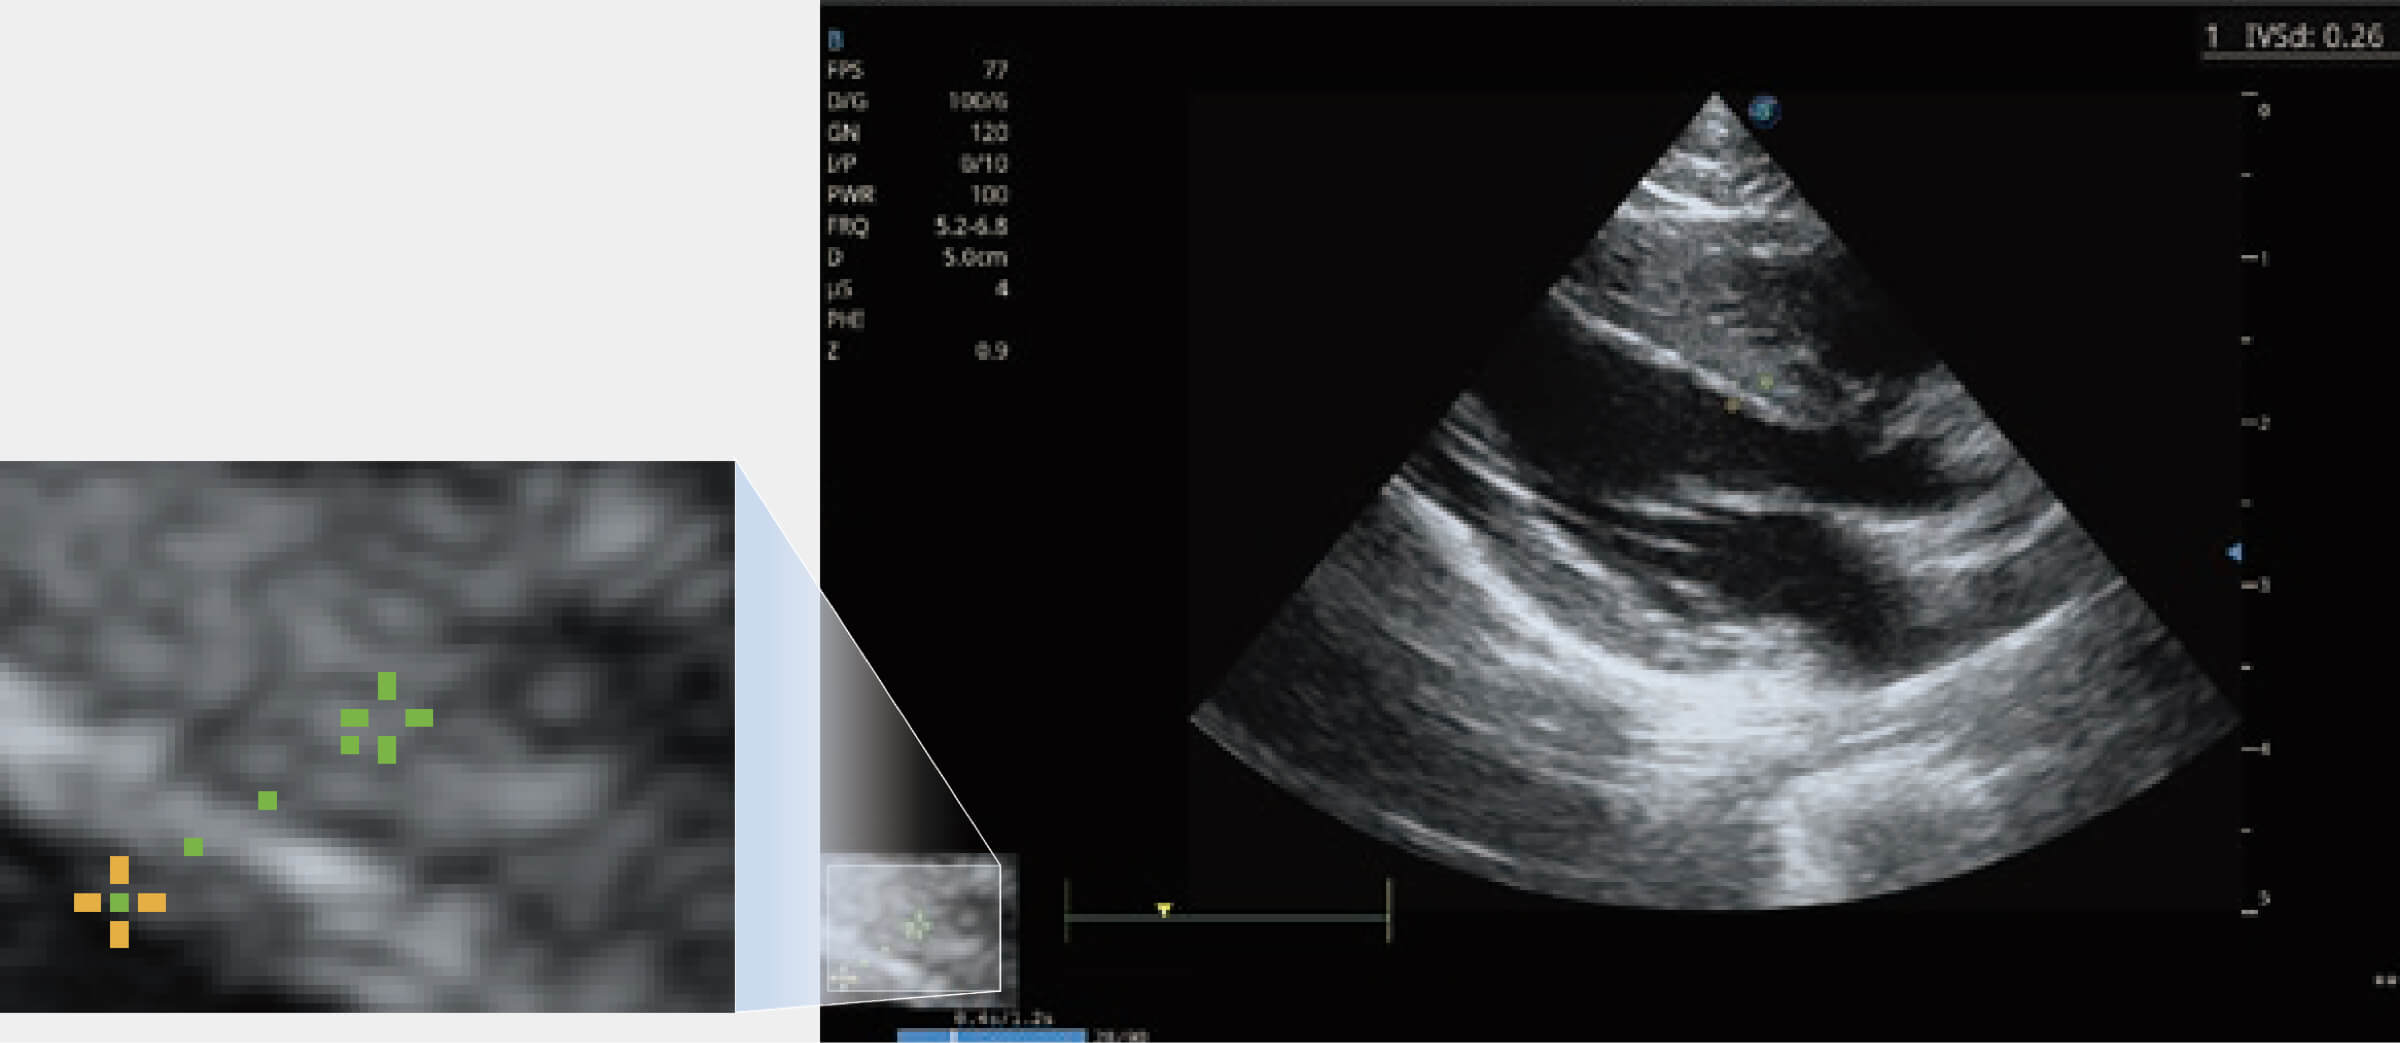

能夠基于左心室壁追蹤和辛普森法,自動(dòng)計(jì)算射血分?jǐn)?shù),支持多個(gè)可移動(dòng)點(diǎn)描跡,與手動(dòng)測(cè)量相比,極大節(jié)省了動(dòng)物醫(yī)生的時(shí)間和精力。

通過(guò)360度任意調(diào)節(jié)3條M型取樣線,在同一心動(dòng)周期上觀察心臟不同位置的運(yùn)動(dòng)曲線,得到準(zhǔn)確的心功能測(cè)量數(shù)據(jù),有效評(píng)估心肌運(yùn)動(dòng)及左心室功能。

當(dāng)心臟測(cè)量結(jié)果超出正常范圍時(shí),可實(shí)時(shí)預(yù)警提示動(dòng)物醫(yī)生,減少疾病漏診概率。